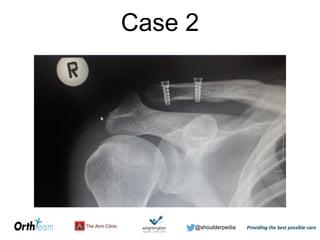

The document discusses AC joint injuries, providing information on mechanisms of injury, grading classifications from I-VI, typical management approaches depending on grade, and two case studies. It notes that AC joint injuries often result from falls on an outstretched hand and outlines the grading system based on ligament disruption and clavicle displacement. While grades I-II are often treated non-operatively and grade III may try non-operative treatment initially, grades IV-VI typically require operative management.